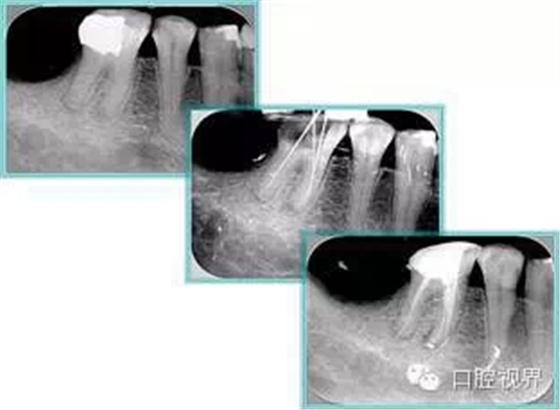

6. 術(shù)后 X 線片

術(shù)后 X 線片用來(lái)評(píng)定根管充填 長(zhǎng)度、致密度(管壁清晰、側(cè)枝)等指標(biāo)。

左圖為根管充填術(shù)后 X 線片。圖中可見(jiàn),根管充填較好。右下圖有白色小點(diǎn),為側(cè)方加壓導(dǎo)致糊劑擠出所致,表明根管充填比較致密。

致密、恰到好處的充填可去除干凈根管里感染灶,機(jī)體逐漸恢復(fù)。

多根牙時(shí)候需進(jìn)行偏移投照,正位投照無(wú)法說(shuō)明具體哪根牙根管充填效果。

7. 器械折斷

右圖及下圖為器械折斷的 X 線片。箭頭處示折斷器械。

解決方法: ( 1 )取出。 ( 2 )通過(guò)。 ( 3 )重新確定工作長(zhǎng)度,充填。 ( 4 )根尖手術(shù)。

器械折斷可以不用取出,取出的原因多是患者心理因素。留在里面的器械關(guān)鍵是進(jìn)行消毒,預(yù)防性使用抗感染藥物,預(yù)防感染。